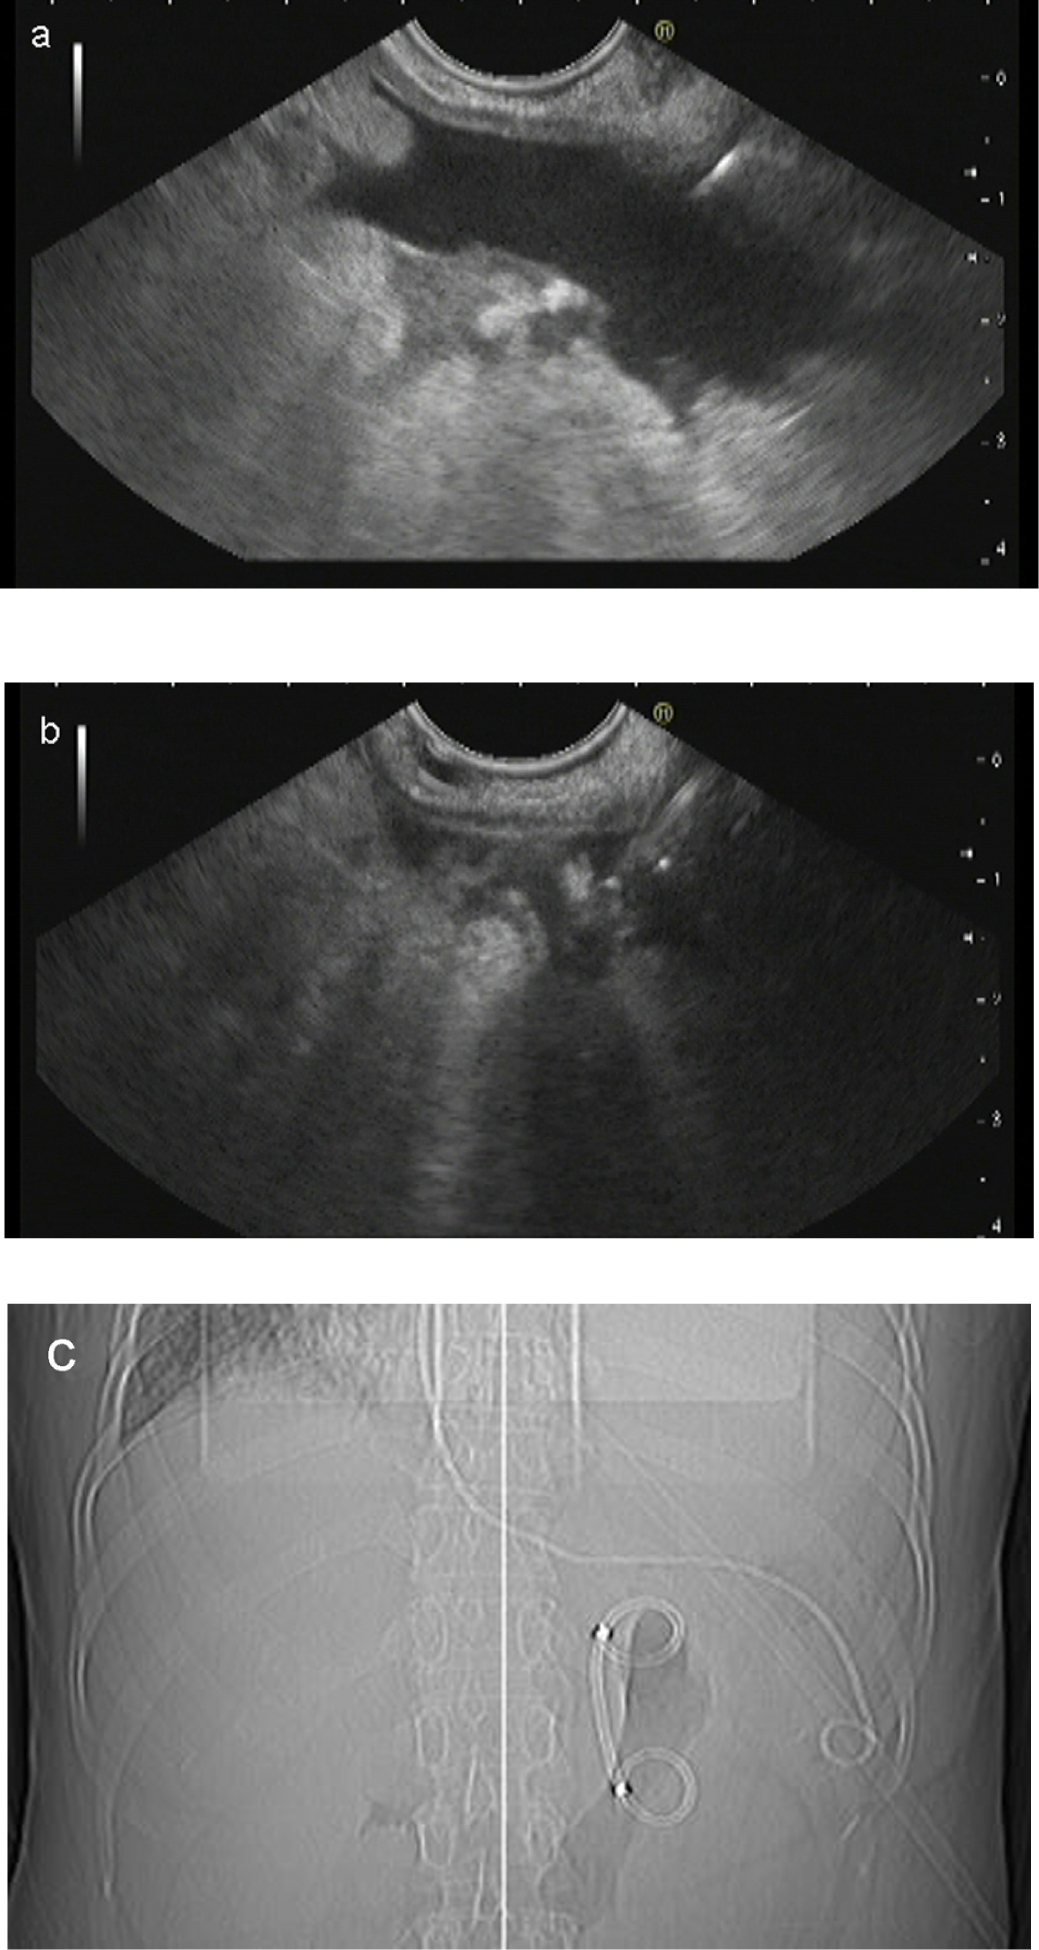

Fifty-two patients were enrolled in this study. The main characteristics of these patients are listed in Table 1. Metal or plastic stents were achieved in 52/52 (100%) of the patients. Massive hemorrhage was observed in two patients during stent placement and was self-limited after the drainage was complete. Plastic stent migration into the cyst was found in one patient 2 weeks after drainage when the patient started to complain of obvious abdominal distention. Migration of the stent into the cyst was detected by CT. In order to retrieve the stent, a new fistula was created under EUS guidance. A regular endoscope was advanced into the cyst, and the stent was retrieved with foreign body forceps. Unfortunately, a devastating cyst hemorrhage occurred during retrieval of the stent. The hemorrhage was stopped using interventional vascular embolization. One patient with a plastic stent experienced leakage of a large amount of cyst fluid into the abdominal cavity after the procedure (Figure 3). The main complaints were abdominal pain and fever. The leakage and symptoms resolved following EUS-guided abdominal drainage with endoscopic nasobiliary drainage (ENBD). Clinical resolution occurred in all 52 (100%) patients in this study (Table 2).

(a) Leakage of a large amount of cyst fluid into the abdominal cavity after the procedure; (b) endoscopic ultrasound-guided abdominal drainage with endoscopic nasobiliary drainage (ENBD); (c) X-ray image after the abdominal drainage.